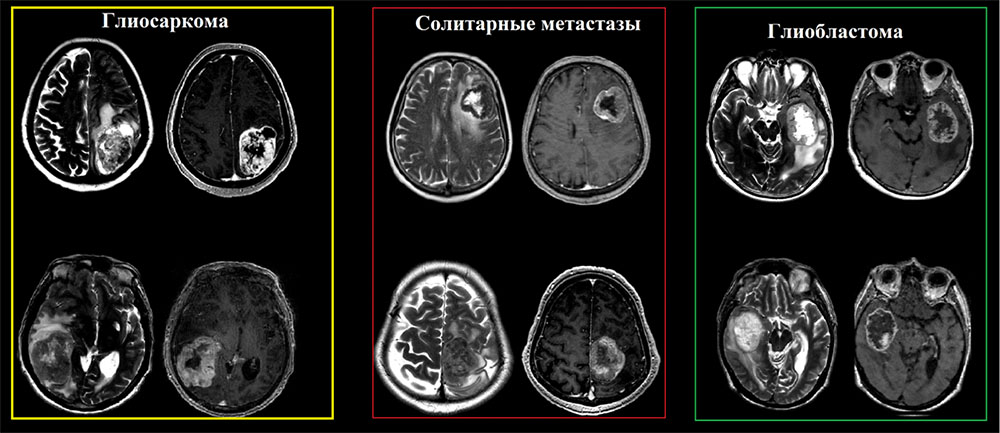

N.В.! В зависимости от количества саркоматозной и глиальной ткани отмечаются вариации, при этом если саркоматозная ткань преобладает, то опухоль подобна метастазу (хорошо отграниченная и плотная), в случае превалирования астроцитарного(нейроглиального) компонента опухоль идентична классической глиоблатоме (Louis DN, Ohgaki H).

Глиосаркома должна быть включена в дифференциальный ряд любой опухоли, которая, по-видимому, является интрааксиальной, но при этом «интимно» прилежит к твердой мозговой оболочки  и демонстрирует гетерогенные визуализационные характеристики на T2-взвешенных изображениях.